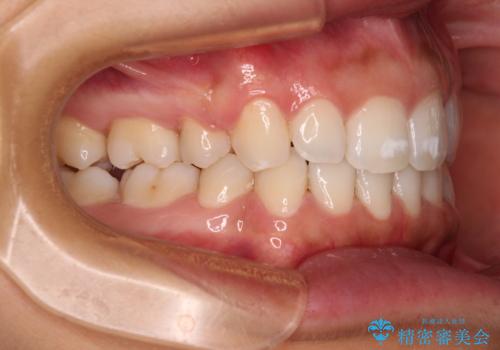

- 出っ歯で唇が閉じにくいとのことで来院された患者様です。

顎先に力を入れないと唇が閉じきれない口元であったので、上下左右の第一小臼歯4本を抜歯して、ワイヤー装置にて矯正治療を行うこととしました。

2年から2年半の治療期間を想定しており、予定通りの期間で無事に終了することができました。

唇や顎先に力を入れないなくてもスムーズに唇を閉じることができるようになりました。